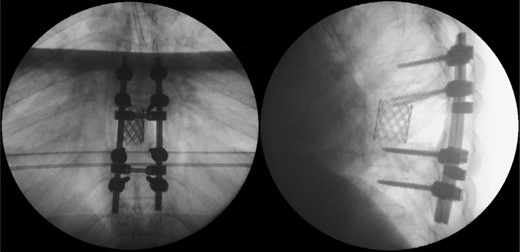

The patient started the pulmonary rehabilitation protocol by the second postoperative day, showing encouraging progression. However, by the third day, she initiated complaints of progressive dyspnea with associated impaired gas exchange. A CT scan confirmed bilateral hemothorax requiring bilateral thoracentesis (Fig. 4), after which she immediately recovered from the previous symptoms.

It was only by the 19th postoperative day, which the patient showed worsening of her general status with fever, dyspnea, decreased gas exchange and an increase in inflammatory markers. A new CT scan was performed, revealing a moderate fluid collection in both lungs, compatible with empyema (Fig. 5). The patient evolved to a septic state, which required her to be transferred to the intensive care unit.

Postoperative thoracic CT scan; large septated empyema, extending from the surgical site to both pleural cavities, was found to be the cause of deterioration of the patient's general condition.